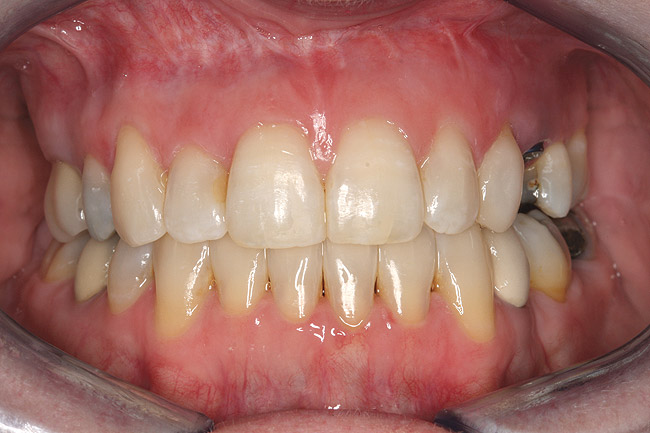

Fig 12 (and Fig 13). Incisors were too upright and had severe incisal wear. He was concerned about esthetics of the worn teeth and his insufficient lip support. Progress photo and panorex 9 months after corticotomies were performed on Nos. 6 through 11. Previous extraction sites were reopened orthodontically to improve function and fill lip support. Incisal edges were restored provisionally with composite resin. Note that despite the creation of adequate spaces to replace missing teeth, there is inadequate room for placement of dental implants because of severe tipping of all the anterior teeth. Osteotomy SFOT may have been a better choice because it would have allowed needed alveoloskeletal correction (without excessive tipping) instead of the primarily dentoalveolar correction common in corticotomy SFOT. Restorative dentist: Brad Jones, DDS.

Figure 12

Fig 13 (and Fig 12). Incisors were too upright and had severe incisal wear. He was concerned about esthetics of the worn teeth and his insufficient lip support. Progress photo and panorex 9 months after corticotomies were performed on Nos. 6 through 11.

Figure 13